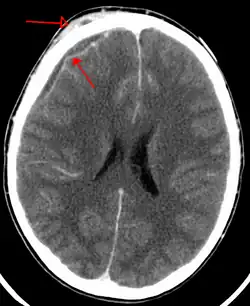

| An abscess that has led to an intracranial subdural empyema as seen on CT | |

Subdural empyema is a form of empyema โ a collection of pus, in the subdural space.

Bacterial or occasionally fungal infection of the skull bones or air sinuses can spread to the subdural space, producing a subdural empyema. The underlying arachnoid and subarachnoid spaces are usually unaffected, but a large subdural empyema may produce a mass effect. Further, a thrombophlebitis may develop in the bridging veins that cross the subdural space, resulting in venous occlusion and infarction of the brain. With treatment, including surgical drainage, resolution of the empyema occurs from the dural side, and, if it is complete, a thickened dura may be the only residual finding. Symptoms include those referable to the source of the infection. In addition, most patients are febrile, with headache and neck stiffness, and, if untreated, may develop focal neurologic signs, lethargy, and coma. The CSF profile is similar to that seen in brain abscesses, because both are parameningeal infectious processes. If diagnosis and treatment are prompt, complete recovery is usual.